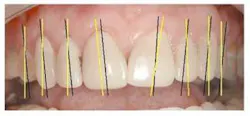

I – Axial Inclination

For the most visually pleasing effect, the teeth should have a slight mesial axial inclination. The observation of our patient's teeth reveals inclinations that do not follow this rule (Fig. 4 – black lines are desired; yellow lines existing).